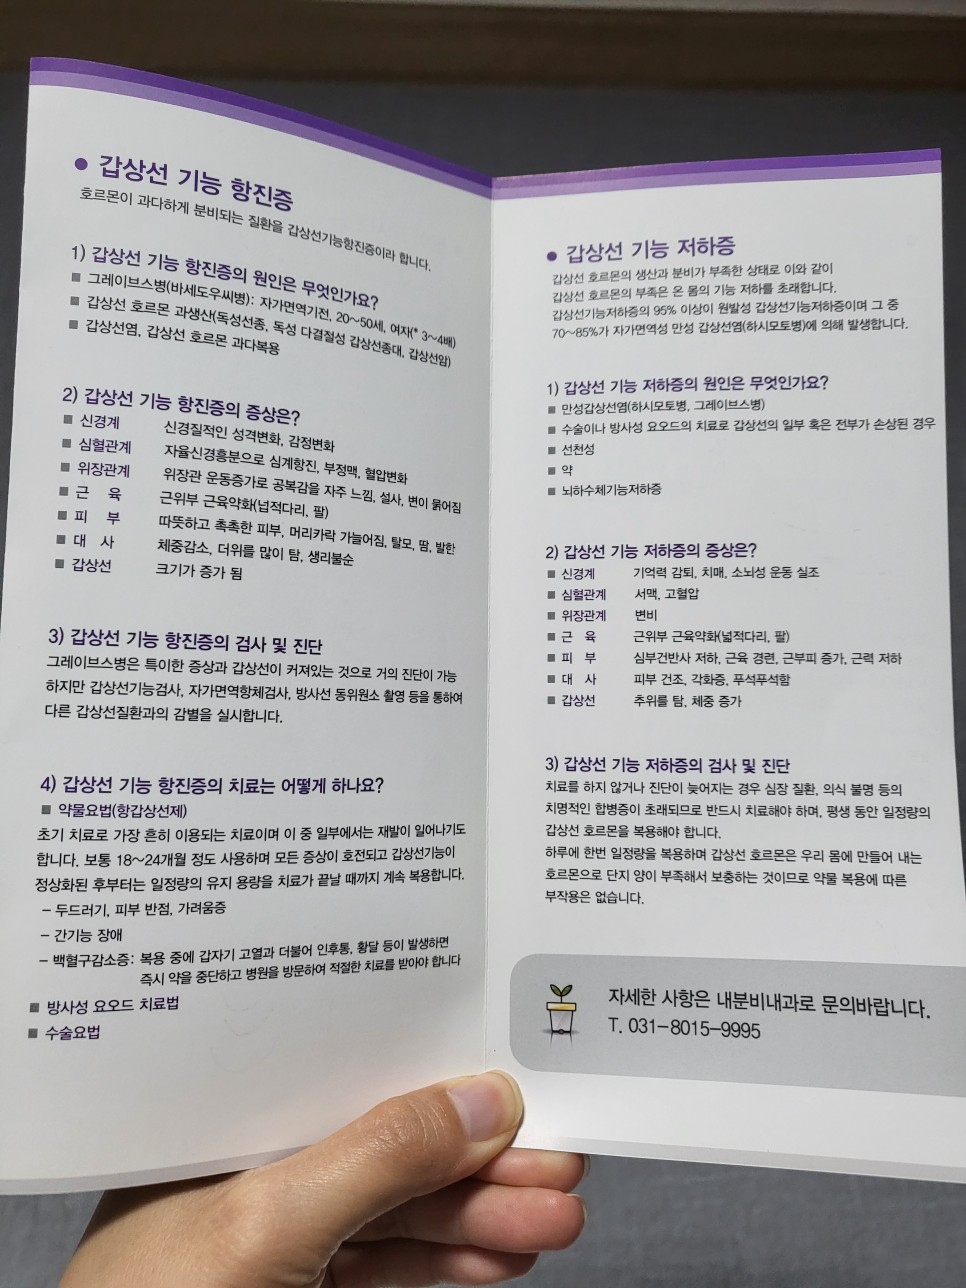

검색과 이전에 회사에 근무했을 때의 기억을 약간 되살려 보면 갑상샘 자극 호르몬이 높은 것은 갑상샘 기능 저하증이라고 할 수 있었다.

어? 왜? 호르몬 수치가 높으면 항진증 아니야?라고 생각할 수 있지만 갑상샘 호르몬과 갑상샘 자극 호르몬은 다르다.

갑상선 자극 호르몬이 많이 분비되는 이유는 갑상선에서 나오는 갑상선 호르몬이 부족하기 때문에 ‘갑상선 기능 저하증’이다.

아, 그리고 갑상선 기능 저하증의 증상으로서는 기본적으로 전신의 기능이 저하한다고 한다.내가 느낀 가장 큰 증상은 추위를 느낀다는 것이다. 몸이 뜨겁고 더위를 많이 타던 나는 잠시 추위를 많이 탔다. 여름인데 난 정말 그런 사람이 아닌데 그리고 무기력증? 정말 아무것도 하고 싶은 것도 없이 집에서 가만히 있었어우울증처럼?

갑상샘(갑상선) 기능 저하증이라고 진단받기 전에는 임신증상인가 했는데, 지금 생각하면 아마 갑상샘 기능 저하증의 증상이었던 것 같다.